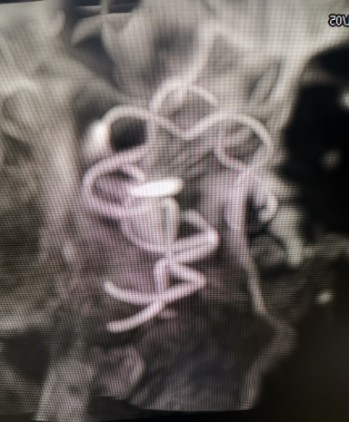

Tubridge®释放过程

锚定后,整体回撤至合适位置后,通过张力释放法缓慢释放支架,直至支架完全打开。观察见支架贴壁良好,动脉瘤颈完全覆盖,遂完全释放支架。

动脉瘤内造影剂滞留,未填弹簧圈。行Xper CT,观察见支架完全打开,贴壁良好。术程顺利结束。